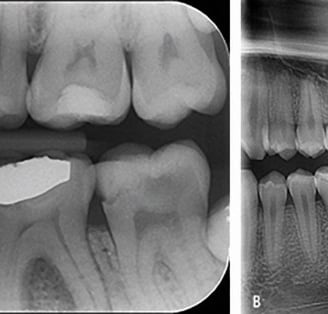

Radiografiile intraorale sunt o modalitate de imagistică care se concentrează pe zone specifice din gura pacientului, oferind imagini detaliate ale dinților, rădăcinilor acestora și a altor structuri orale. Aceste radiografii sunt utilizate pentru diagnosticarea cariilor, afecțiunilor pulpare, bolii parodontale și a altor probleme dentare. Există mai multe tipuri de radiografii intraorale, fiecare având aplicații specifice.

Diagnosticul cariilor dentare: Aceste radiografii ajută la identificarea cariilor și la planificarea tratamentelor de restaurare.

Endodonție: Radiografiile intraorale sunt utile în endodonție pentru a identifica leziuni pulpare și pentru a ghida tratamentele de canal radicular.

Extracții dentare: În cazul extracțiilor dentare, radiografiile intraorale pot ajuta medicul stomatolog să evalueze rădăcinile dentare și să planifice procedura.